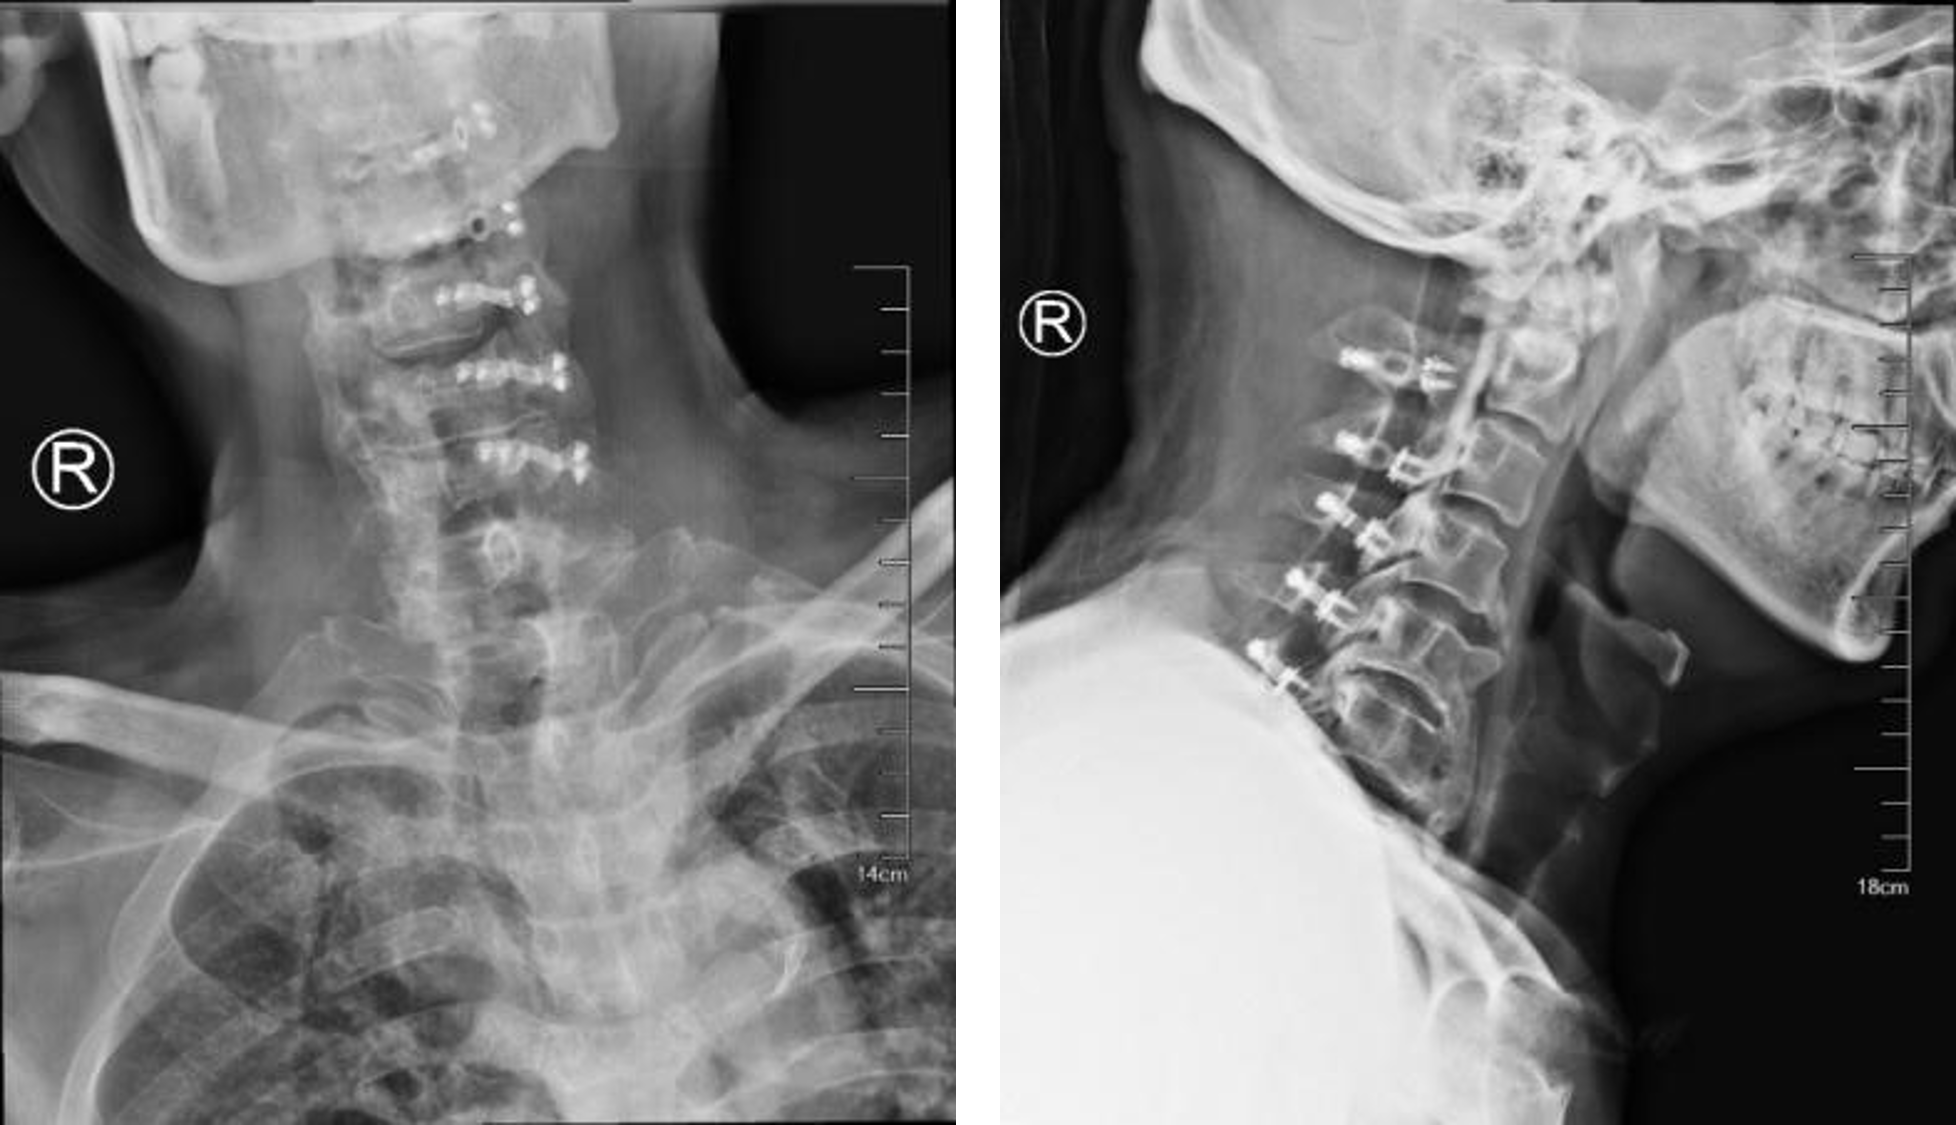

所以在C1~2处手术,无异于在刀尖上起舞。在与家属充分沟通后,我院骨科决定行颈1后弓切除+椎后路单开门椎管扩大成形术(C2~6),这种方案巧妙地避开了增生的骨赘,在颈椎后方“开一道门”,减少了切除骨赘而可能导致的神经损伤,给受压的神经释放出足够的空间。姜为民主任亲自上阵,王喜安副主任医师及团队成员紧密配合,一切按计划有序进行。

经过三个多小时的精细操作,手术顺利地完成了。术后第一天,王先生高兴地说:“我很明显地感觉到自己的手脚轻松了,就好像有什么压着的东西被去掉了,来苏州开刀真是选对了!”而后在骨科护士长张霞芬护理团队的精心护理下,老人家恢复得很快,术后一周就顺利出院了。